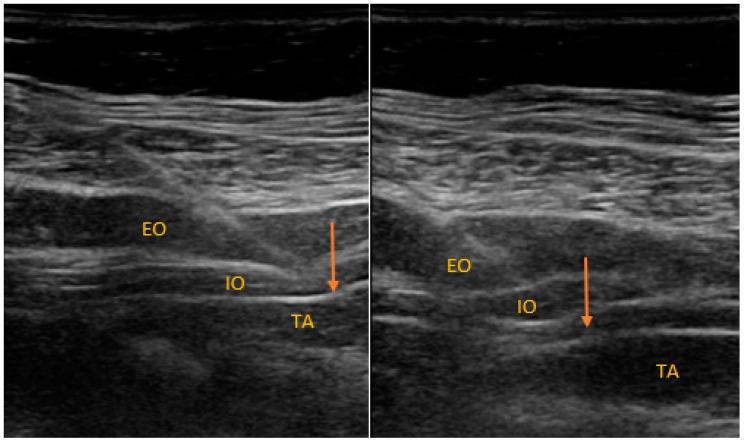

Acute pain intensity related to cesarean section (CS) may be extensive and is often underestimated. This may influence mothers' quality of life and their children's development. Regional analgesia techniques that include transversus abdominis plane block (TAPB) and quadratus lumborum block (QLB) have proven their efficacy in the postoperative period after CS. Although several randomized controlled studies and one meta-analysis have investigated the utility of TAPB and QLB in the reduction of acute and chronic pain after CS, only one study directly compared both types of regional blocks and revealed superiority of QLB over TAPB. Our study aimed to reevaluate the effectiveness of transversus TAPB and QLB in controlling acute postoperative pain after CS. We recruited 197 women with singleton pregnancies undergoing CS under spinal anesthesia. The patients were randomized to receive either TAPB or QLB after CS. The acute postoperative pain was evaluated using the visual analog scale (VAS) at 2, 4, 8, 12 and 24 h after the operation. No significant difference in acute postoperative pain intensity between the groups was found. The patients who received TAPB had a higher demand for supplemental morphine injections ( < 0.039). In our study, none of the evaluated regional blocks demonstrated an advantage over the other regarding acute postoperative pain management.

剖宫产术后(CS)的急性疼痛强度可能较大,且往往被低估。这可能会影响产妇的生活质量及其子女的发育。已经证明,包括腹横肌平面阻滞(TAPB)和腰方肌阻滞(QLB)在内的区域镇痛技术在 CS 后的术后期间有效。尽管已经有几项随机对照研究和一项荟萃分析调查了 TAPB 和 QLB 在减少 CS 后急性和慢性疼痛方面的作用,但只有一项研究直接比较了这两种类型的区域阻滞,并显示 QLB 优于 TAPB。我们的研究旨在重新评估 TAPB 和 QLB 在控制 CS 后急性术后疼痛方面的有效性。我们招募了 197 名接受脊髓麻醉下 CS 的单胎妊娠女性。患者在 CS 后被随机分配接受 TAPB 或 QLB。术后 2、4、8、12 和 24 小时使用视觉模拟量表(VAS)评估急性术后疼痛。两组之间的急性术后疼痛强度无显著差异。接受 TAPB 的患者对补充吗啡注射的需求更高(<0.039)。在我们的研究中,在急性术后疼痛管理方面,没有一种评估的区域阻滞方法比其他方法具有优势。